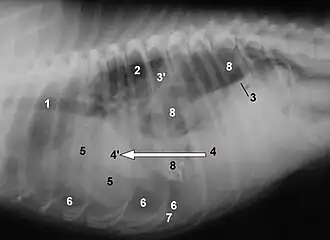

Röntgenaufnahme einer rechtsseitigen Zwerchfellruptur beim Hund mit Verlagerung von Leber (4), Milz (7) und Magen (8). 3 zeigt auf die erhaltene linke Zwerchfellansatzlinie.

Infolge erhöhter Drücke in einer der beiden Körperhöhlen kann es zu Lageveränderungen des Zwerchfells kommen. Ein erhöhter Druck in der Bauchhöhle führt zu einem Zwerchfellhochstand, zum Beispiel bei Lebervergrößerung, Milzvergrößerung, Magenüberladung, Tumoren oder Schwangerschaft. Ein Zwerchfelltiefstand kann durch eine obstruktive Lungenerkrankung oder einen Pleuraerguss entstehen. Bei diesen Lageveränderungen des Zwerchfells ist die Atmung eingeschränkt.

Eine Verletzung des Zwerchfells, zum Beispiel eine Durchbohrung (Perforation) oder eine Zwerchfellruptur, kann lebensbedrohliche Folgen haben, wenn dadurch kein Unterdruck im Brustraum erzeugt werden kann (Pneumothorax). Zudem kann die Perforation des Zwerchfells, beispielsweise bei Schussverletzungen oder bei Messerstichen, auch in die Bauchhöhle führen.[5] Dies hängt von der Richtung und Länge der Wunde sowie In-/ Exspirationsstellung im Augenblick der Verletzung ab; besonders kritisch sind Verletzungen der vorderen Brustwand in Höhe des 5. und des 6. Intercostalraums.[5]